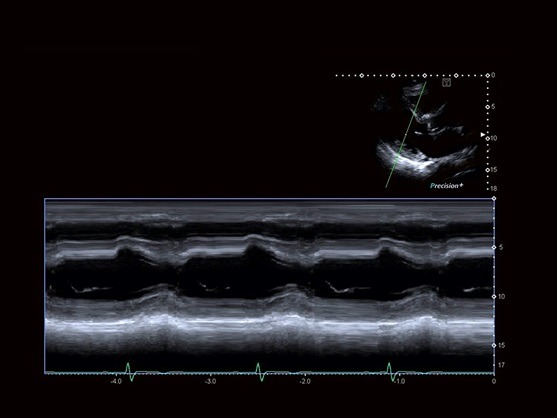

Flex-M به شما اجازه می‌دهد که رد های آناتومیک درستی را در تصویر M mode از روی تصاویر زنده یا ذخیره شده با کیفیت یکسان به دست آورید

تکنولوژی پردازش سیگنال و پروب های با پهنای باند وسیع Aplio حساسیت، نفوذ و قدرت تفکیک مکانی فوق العاده را برای تمام حالات داپلر به ارمغان می آورد.